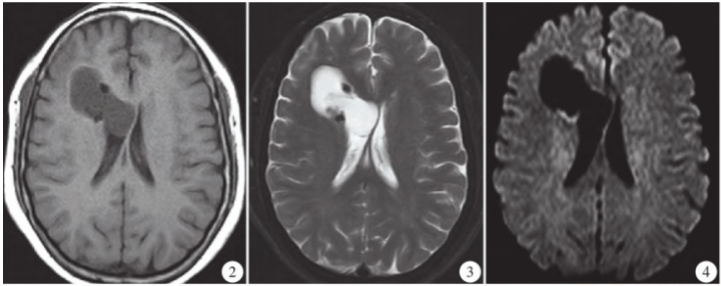

MRI平扫显示右侧额叶不规则团块状混杂信号影,大小约4.3 cm×3.7 cm×4.0 cm,呈T1WI低T2WI稍高及FLAIR稍高信号为主,其间见结节状T1WI低T2WI低FLAIR低信号,病灶向内凸向脑组织,深达右侧脑室旁(图2~4);增强扫描病灶中心无强化,部分壁轻度强化(图5~7);考虑右侧额叶囊性肿瘤性病变并钙化。

图2~4 MRI平扫显示右侧额叶及侧脑室旁不规则团块状混杂异常信号,T1WI/TRA稍低信号,T2WI/TRA呈高信号,DWI低信号,病变内见结节状低信号。